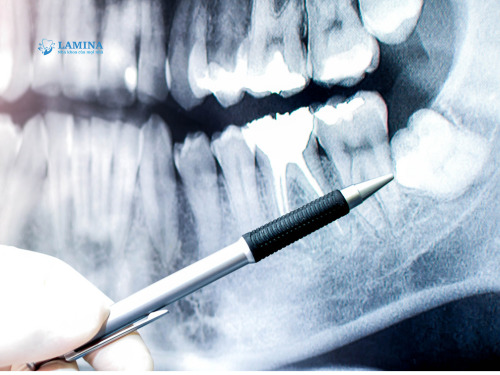

Thực tế, X-quang là bước bắt buộc trước khi can thiệp răng khôn, vì nó giúp bác sĩ nhìn thấy toàn bộ chân răng, dây thần kinh và xương hàm — những thứ mắt thường không thể quan sát.

Khi nhổ răng khôn, bác sĩ cần biết chính xác hướng mọc, vị trí chân răng và khoảng cách tới dây thần kinh hàm dưới. Việc này chỉ có thể thực hiện thông qua phim x quang.

Ví dụ, có những trường hợp răng khôn mọc ngầm sâu, chỉ lệch vài độ cũng đủ khiến bệnh nhân bị tê nửa mặt sau nhổ — nếu không có phim x quang, bác sĩ không thể lường trước.

Ví dụ, nếu phim cho thấy răng khôn nằm sát dây thần kinh, bác sĩ sẽ chọn kỹ thuật tách thân răng hoặc nhổ từng phần thay vì rút nguyên chiếc — vừa an toàn, vừa giảm đau.